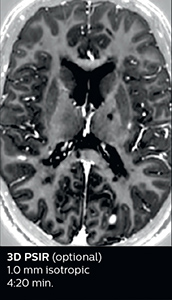

Fast MS protocol with optional sequences

The abbreviated MS protocol for brain is only around 9 minutes, so in case of suspected multiple sclerosis, one or two more advanced sequences may be added, such as PSIR (phase sensitive inversion recovery) or susceptibility-weighted sequences to help us make more confident diagnoses in these inflammatory cases.

3D PSIR